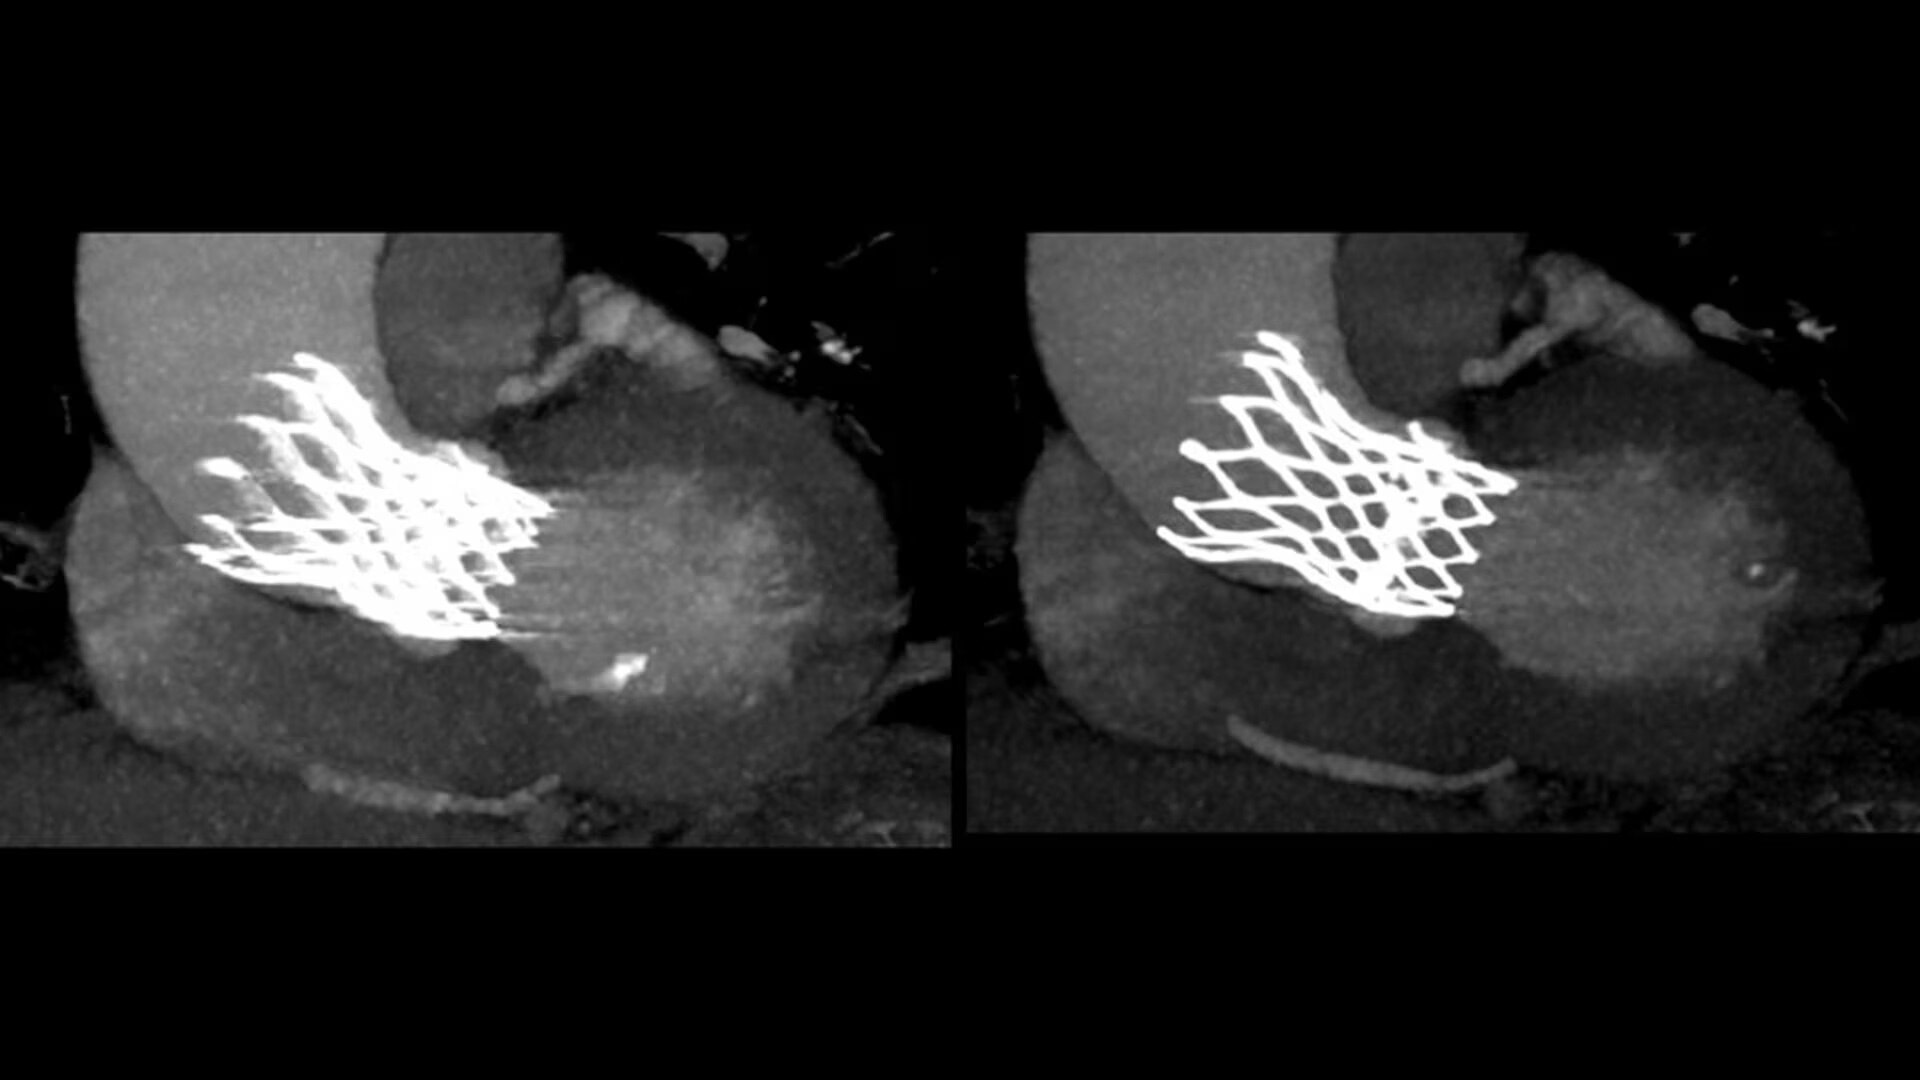

SnapShot Freeze 2

Intelligent and automated whole-heart motion correction for enhanced Cardiac CT imaging.

Motion correction

6x reduction in motion artifacts1

Temporal resolution

19.5 msec effective temporal resolution at 0.23s/rotation gantry speed2

Automated

Whole-heart motion correction